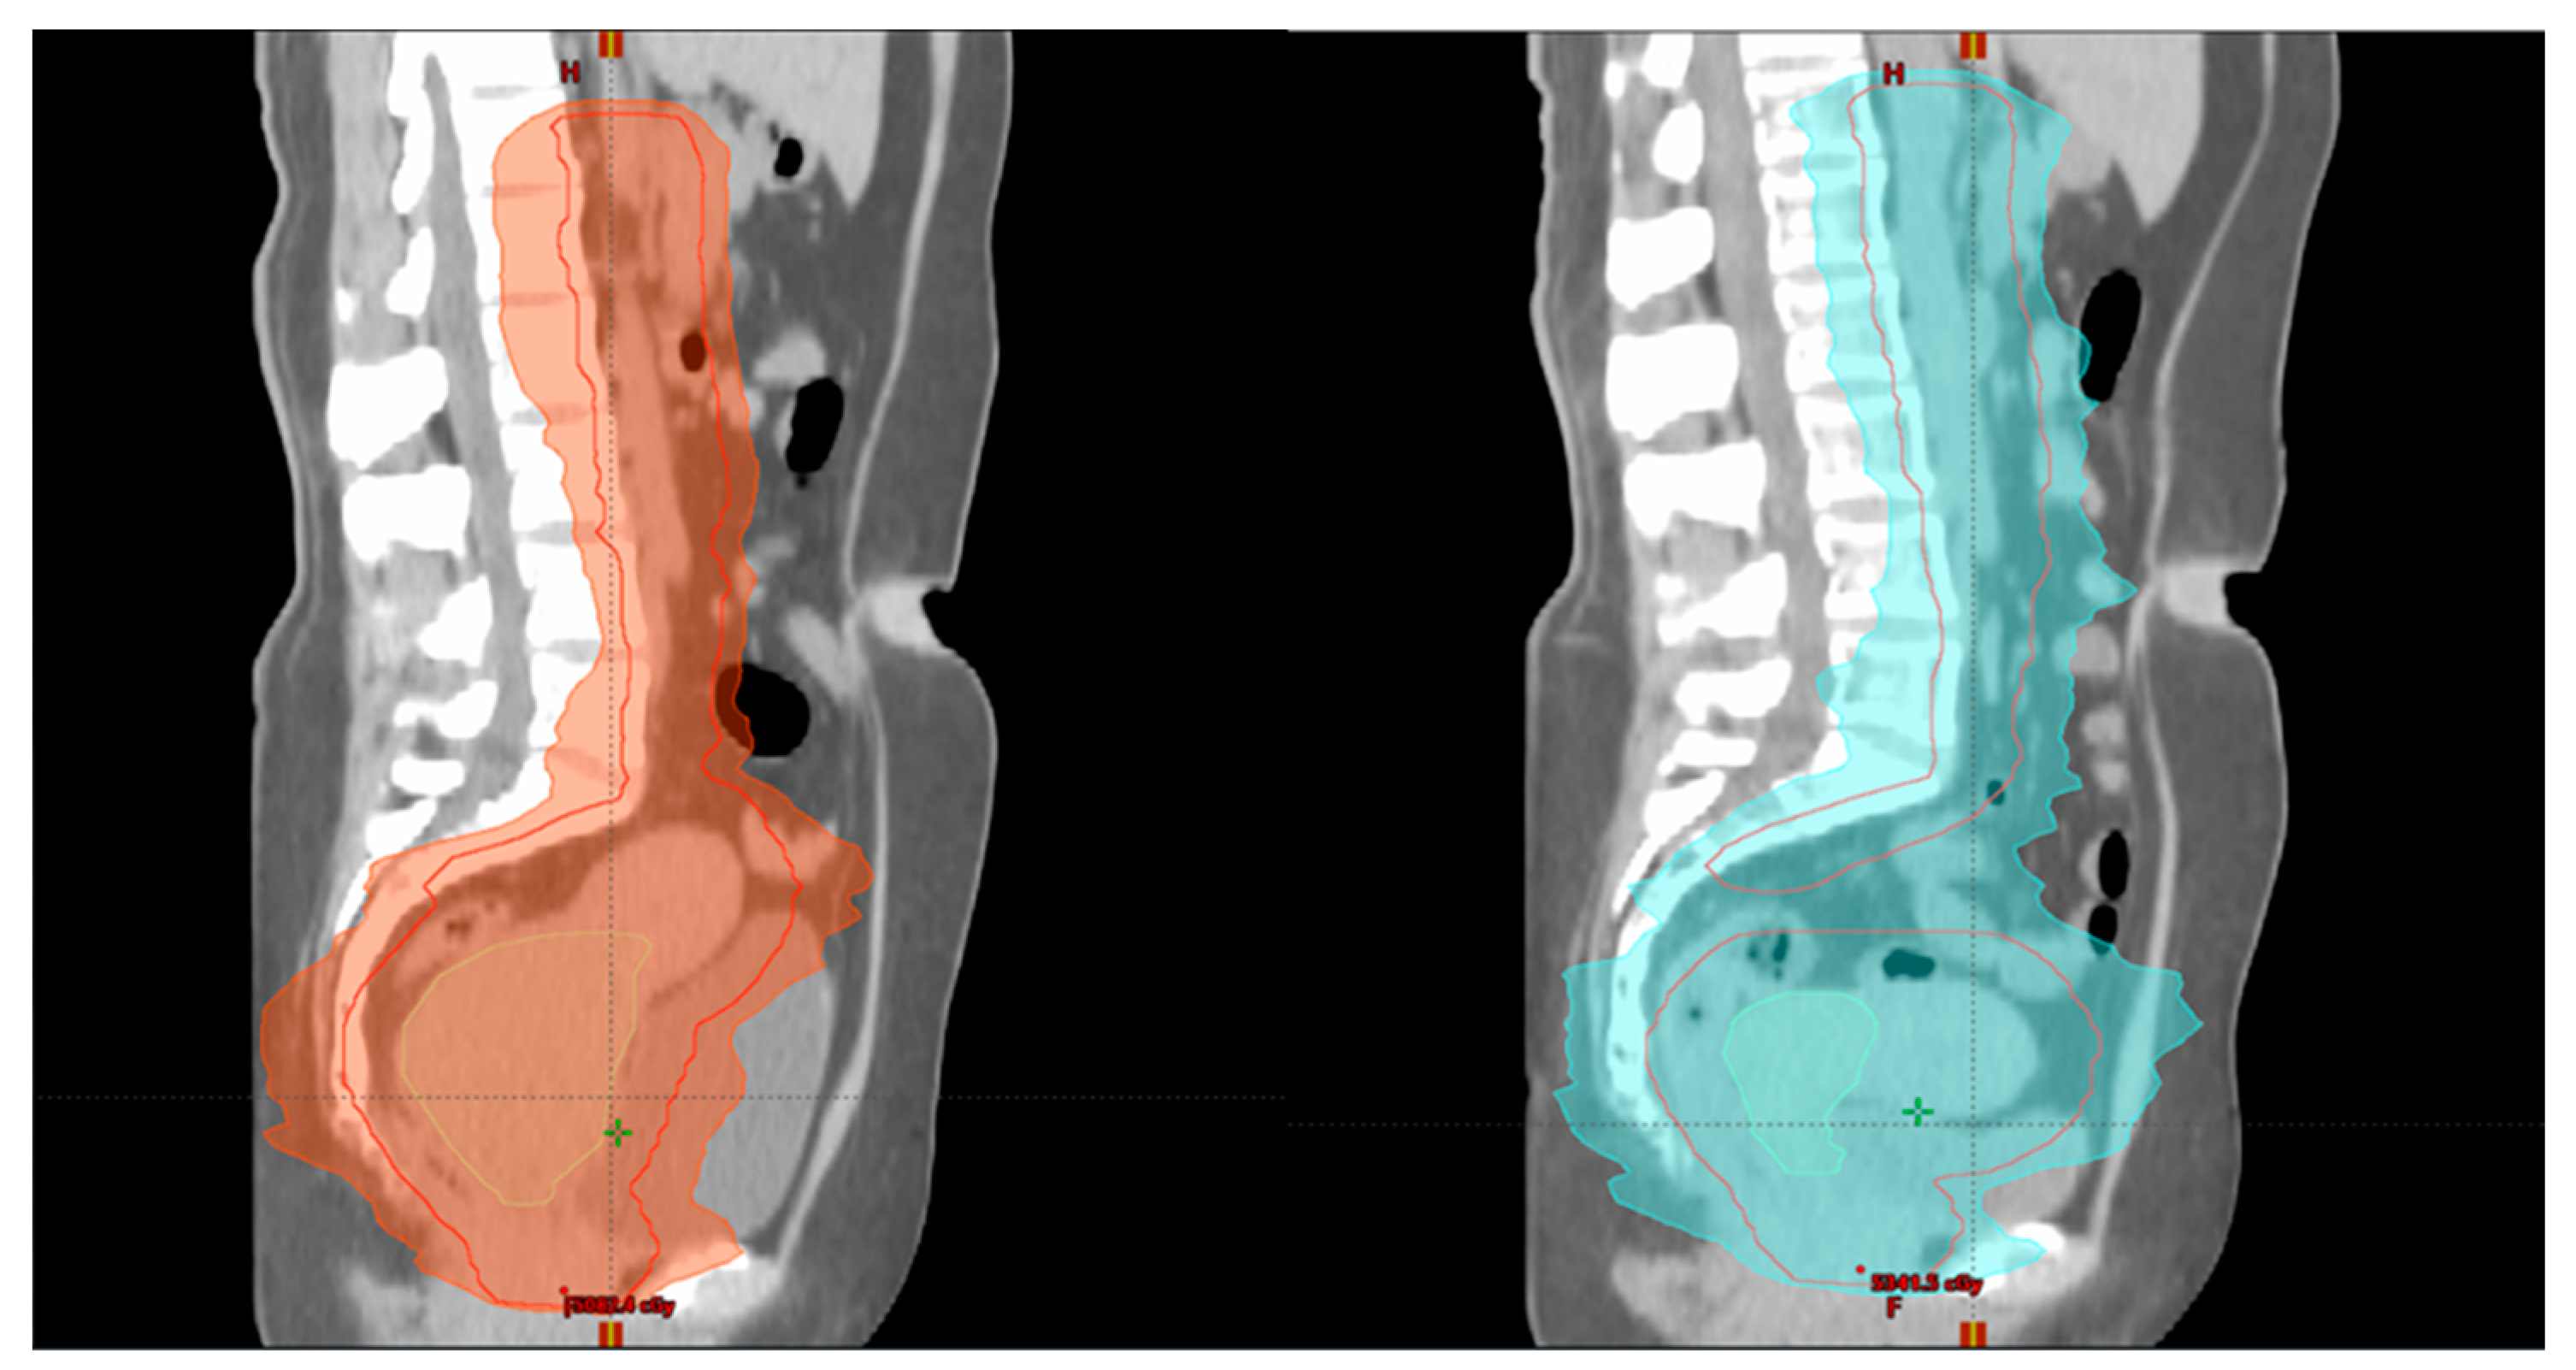

3.2. Intensity-Modulated Radiotherapy (IMRT) Volumetric Intensity-Modulated Arcs (VMAT)

3.3. Adaptive External Beam Radiotherapy